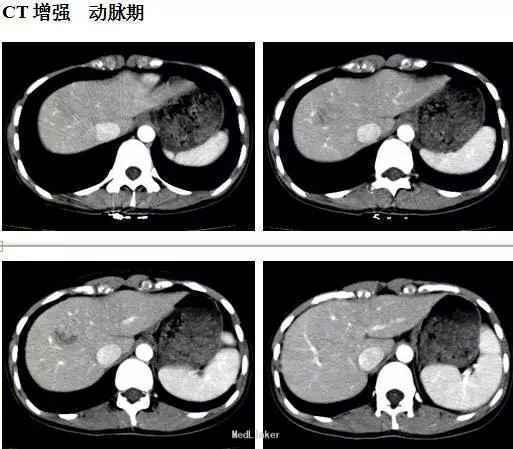

体检:腹平软,无肠型及蠕动波,未见腹壁静脉曲张,肝脾肋下未及,肝区无叩击痛,全腹无压痛、反跳痛、肌紧张。腹水征阴性。 CT表现:肝右前叶可见类圆形等低混杂密度影,边界尚清,直径约2.5cm,CT值-20~35HU,;增强后动脉期病灶呈结节样强化,门脉期病灶包膜强化更明显,有逐渐向中心填充趋势。

初步诊断:肝血管瘤。原拟定期复查,但患者强烈要求手术治疗,遂予肝部分切除术,术中所见也考虑血管瘤可能,术后恢复可。术后病理: 肝脏血管平滑肌脂肪瘤。免疫组化: melan-A(+)、HMB-45(+)、SMA灶性(+)、actin灶性(+)、S-100(-)、CK(-)、Desmin(-)、Ki-67阳性细胞约2%。